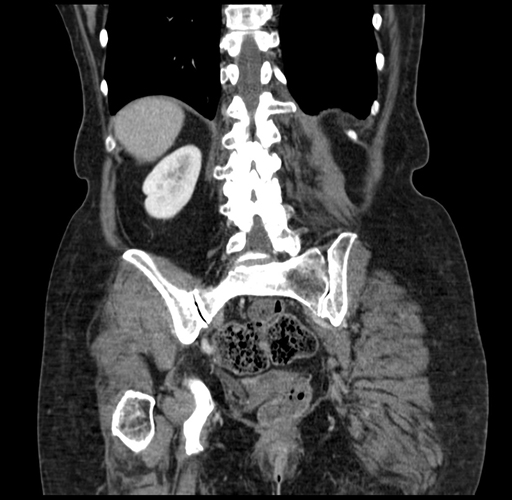

Coronal Venous